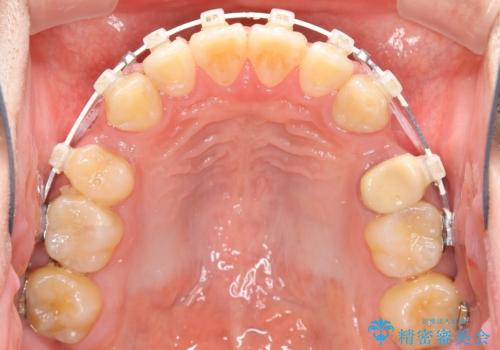

- 矯正装置

- 審美装置

今回のような歯の移動量が大きい場合、インビザライン治療では歯が傾いてしまう場合があります。

また、かみ合わせが深い方の場合、インビザライン治療によってさらにかみ合わせが深くばってしまう場合があります。

ワイヤー治療では歯の傾きを抑えながら大きい距離の移動が可能で、かみ合わせが深くなるリスクも少ないです。